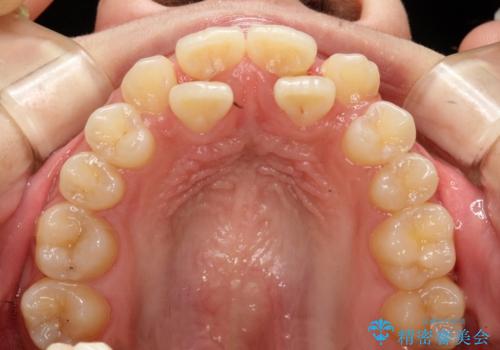

- 上下の前歯に激しい段差がある**重度の叢生(がたつき)**を主訴にご来院されました。精密検査の結果、歯をきれいに並べるためのスペースが圧倒的に不足していたため、上下左右の4番目の歯(第一小臼歯)を計4本抜歯する計画を立案しました。

本症例では、まず抜歯した大きなスペースを効率よく使い、歯の根元から大きく動かす必要があるため、初期段階にワイヤー矯正を採用。その後、細かな噛み合わせの調整や仕上げにインビザラインを使用する「ハイブリッドな矯正治療」で、期間の短縮と精度の高い仕上がりを目指しました。

治療は、それぞれの装置のメリットを最大限に活かす2ステップで進めました。

ワイヤー矯正による先行治療: 最初のステージでは、ワイヤー装置を使用して抜歯したスペースへ歯を大きく移動させました。重度の叢生の場合、ワイヤーを用いることで歯のねじれや大きな移動をスピーディーに行うことができ、治療期間の短縮につながります。

インビザラインによる精密な仕上げ: 全体のがたつきが概ね整った段階で、インビザライン(マウスピース矯正)へ移行しました。透明で目立たないマウスピースを使用しながら、0.1mm単位の細かな歯の配置や、最終的な咬み合わせのバランスを精密に整えていきました。

治療の結果、重度のがたつきは跡形もなく解消され、抜歯したスペースもきれいに閉じました。ワイヤーによる「確実な移動」と、インビザラインによる「緻密な仕上げ」を組み合わせることで、審美性と機能性の両立を叶えた美しい歯並びを実現しました。